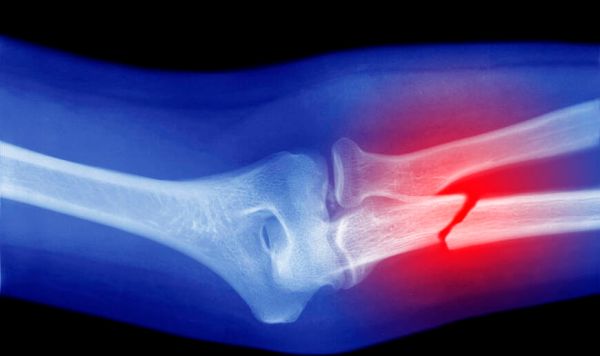

Çinli araştırmacılar, kemik kırıklarını yalnızca 3 dakika içinde sabitleyebilen yenilikçi bir "kemik yapıştırıcısı" geliştirdi. “Bone-02” adı verilen bu biyolojik yapıştırıcı, özellikle ıslak ve kanlı cerrahi ortamlarda bile güçlü tutunma sağlayarak, geleneksel vidalama ve plaka yöntemlerine alternatif olabilir.

Araştırmacılar, yapıştırıcının istiridyelerin su altında yüzeylere yapışma mekanizmalarından ilham alındığını belirtiyor. Geliştirilen yapıştırıcı, kırık kemik parçalarını hızlıca birleştirip sabitliyor, ardından vücut tarafından zamanla emilerek herhangi bir yabancı cisim kalıntısı bırakmıyor.